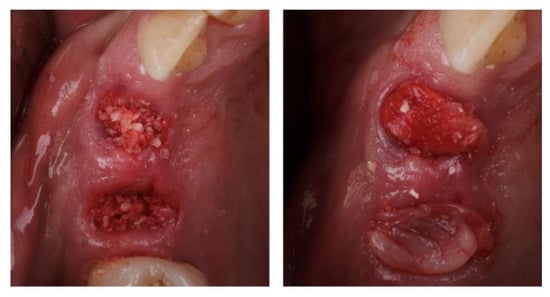

2.3. Surgical Procedure

2.4. Radiographic Examination